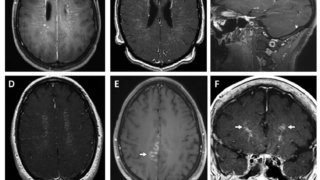

下垂体MRIでは前葉が軽度萎縮もしくは正常。

下垂体MRIでは明らかな異常が認められないため、原因不明の中枢性甲状腺機能低下症と診断されることが多い。しかし、造影MRIを行うと一部の患者では不均一な増強を伴うわずかに萎縮した下垂体前葉が認められる。